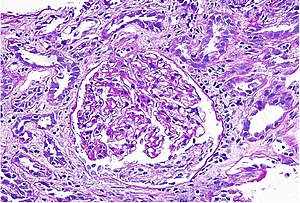

Acute interstitial nephritis on light microscopy

a,b)Microscopy of renal biopsy shows acute interstitial nephritis

While non-invasive patient evaluation (physical examination, blood and urine testing, imaging studies) can be suggestive, the only way to definitively diagnosis interstitial nephritis is with a tissue diagnosis obtained by kidney biopsy. Pathologic examination will reveal the presence of interstitial edema and inflammatory infiltration with various white blood cells, including neutrophils, eosinophils, and lymphocytes. Generally, blood vessels and glomeruli are not affected. Electron microscopy shows mitochondrial damage in the tubular epithelial cells, vacuoles in the cytoplasm, and enlarged endoplasmic reticulum.[21]